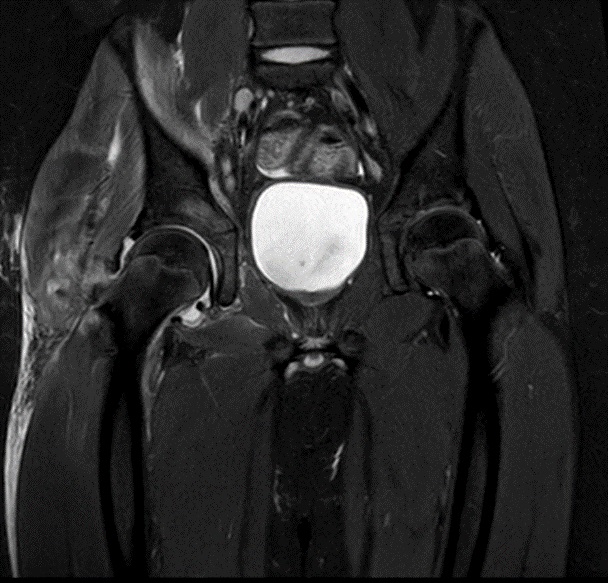

Se realiza un hemograma con leucocitosis de 14 550/mm3 (10 630/mm3 neutrófilos, 2300/mm3 linfocitos) y una proteína C reactiva (PCR) de 69,9 mg/l, así como líquido articular en la ecografía de partes blandas (Fig. 1) y en la resonancia magnética (RM) derrame articular de cadera derecha con engrosamiento sinovial y afectación acetabular con edema de los músculos obturadores y psoas-ilíaco ipsilaterales (Fig. 2), datos sugestivos de artritis de cadera.

| Figura 2. Resonancia magnética de caderas: aumento de señal por engrosamiento sinovial y afectación acetabular derecha con edema que se extiende hacia la rama iliopubiana y los músculos obturadores y psoas-ilíaco ipsilaterales |